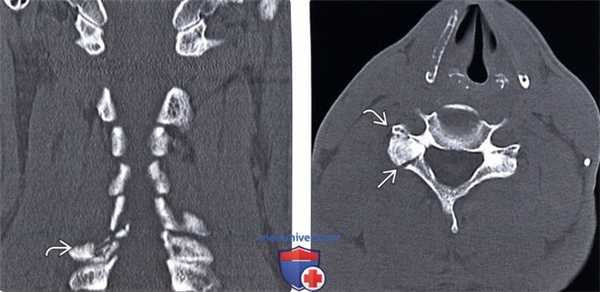

(Слева) КТ, фронтальный срез, пациент с гиперэкстензионно-ротационным повреждением шейного отдела позвоночника: односторонний оскольчатый перелом правой суставной колонны С7 с незначительным смещением фрагментов.

(Справа) КТ, аксиальный срез: перелом правой суставной колонны В и пластинки дуги С6, приводящий к травматической сепарации суставной колонны.